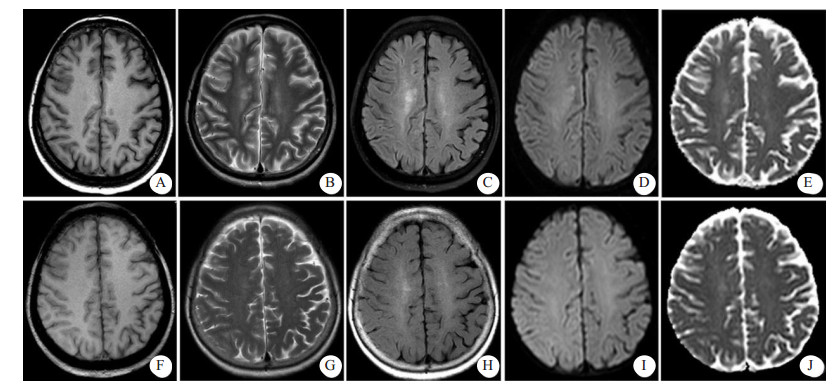

患者女性,71岁,2011年3月行食管癌切除术,6年来反复出现咯血症状,每次均在止血及抗感染治疗后好转。2018年1月20日患者再次出现咯血,入苏州大学附属第二医院介入科治疗。CT检查提示支气管扩张伴感染,遂于2018年1月25日在本院行支气管动脉栓塞术,分别对右支气管动脉远端、支气管动脉主干及左侧肋间动脉进行栓塞,术中使用的造影剂为碘海醇150 mL(浓度为30 g/100 mL)。术后仍出现反复痰中带血,因症状逐渐加重,患者于2018年8月13日再次来本院就诊。患者既往无高血压、糖尿病、心脏病等慢性病病史。入院后,给予患者头孢匹胺抗感染及止血、抑酸等对症支持治疗,咯血症状明显缓解。为进一步明确患者支气管动脉情况并予以处理,于8月17日穿刺右股动脉对患者施行支气管动脉造影+栓塞术,造影显示左侧两支支气管动脉与肋间动脉共干,左侧一支气管动脉血管明显增粗,紊乱,可见小片状可疑出血染色,遂对左侧两支与肋间动脉共干的支气管动脉分别予以栓塞,术中使用的造影剂为碘海醇100 mL(浓度为30 g/100 mL)。术中患者未有不适,术后患者安返病房。术后2 h, 患者无明显诱因下突然出现谵妄,查体:T 36.6℃,P 110次/min,BP 190/80 mmHg (1 mmHg=0.133 kPa),双侧瞳孔对光反射存在,左上肢肌力1级,右上肢肌力5级。急诊颅脑CT显示,右侧脑沟裂、纵裂池密度增高,局部脑实质肿胀、密度增高(图 1)。术后4 h颅脑MRI显示,右侧额叶部分皮质增厚,皮质T1WI信号稍减低,T2WI、T2WI-FLAIR、DWI信号增高,ADC信号稍高;右侧放射冠区见斑片状T1WI稍低信号,T2WI、T2WI-FLAIR、DWI高信号,ADC稍高信号影(图 2A~E);颅脑与颈部TOF-MRA显示各动脉未见明显扩张或狭窄征象。结合患者临床及影像学表现,在排除心脑血管病变后,经多学科会诊,考虑造影剂脑病。给予患者糖皮质激素抗炎、甘露醇降颅压、改善微循环及纠正电解质紊乱等对症处理,患者于术后第3天意识恢复,左侧肢体肌力明显好转。术后第6天,患者精神状态与左侧肢体肌力完全恢复,复查颅脑CT显示脑沟裂池内及局部脑实质高密度影消失,MRI各序列(图 2F~J)未见明显异常,予以出院,随访至今,患者未有不适。

| 患者介入栓塞术后4 h(A~E),示右侧额叶部分皮质增厚,皮质T1WI信稍稍减低,T2WI、T2WI-FLAIR、DWI信号增高,ADC信号稍高;右侧放射冠区见斑片状T1WI稍低信号,T2WI、T2WI-FLAIR、DWI高信号,ADC稍高信号影。患者出现症状后第6天复查(F~J)示颅脑已基本显示正常 图 2 患者颅脑MRI检查结果 |

临床表现轻微的造影剂脑病,影像学检查可以无异常发现。对于症状较为严重的患者,颅脑CT平扫及MRI检查常可见特征性表现。造影剂脑病的CT表现可以为脑水肿,皮质及皮质下异常高密度影,蛛网膜下腔密度增高以及局灶性高密度改变等[2, 6]。但是,有些造影剂脑病患者虽然症状严重,CT平扫也可无异常发现[4]。CT上脑实质的异常高密度影在MRI上可以表现为T2WI、DWI及FLAIR高信号灶,而ADC可无明显异常[3, 6]。这些异常的影像学表现均会在临床对症治疗后短期内消失。本例患者的CT及MRI表现与文献报道相符。

造影剂脑病需与部分脑血管疾病相鉴别,主要是蛛网膜下腔出血和急性缺血性梗死。蛛网膜下腔出血与造影剂脑病在CT上都可以表现为脑沟裂池内高密度影,但出血的CT值一般为40~60 HU,而进入脑沟裂池的造影剂CT值约为80~160 HU[3]。造影剂脑病的异常高密度影会在24~48 h内变淡甚至消失,但出血的高密度影常可持续数天至数周。不同时期的蛛网膜下腔出血在T2WI-FLAIR上均可表现为脑沟内高信号[7],而本例CT图像中脑沟裂池内的高密度影在T2WI-FLAIR上表现为与正常脑脊液类似的低信号。造影剂脑病患者可以出现类似急性缺血性梗死导致的头痛、偏瘫等神经系统症状,但急性缺血性梗死在ADC上表现为低信号,颅脑TOF-MRA常可见到脑血管的局限性狭窄或闭塞,本例患者ADC信号未见降低且颅脑TOF-MRA未见明显异常。